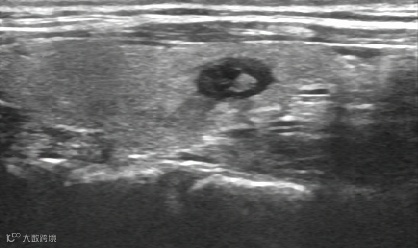

腱鞘囊肿抽液治疗:

治疗前,囊肿大小11X10mm。

治疗后,囊肿消失。